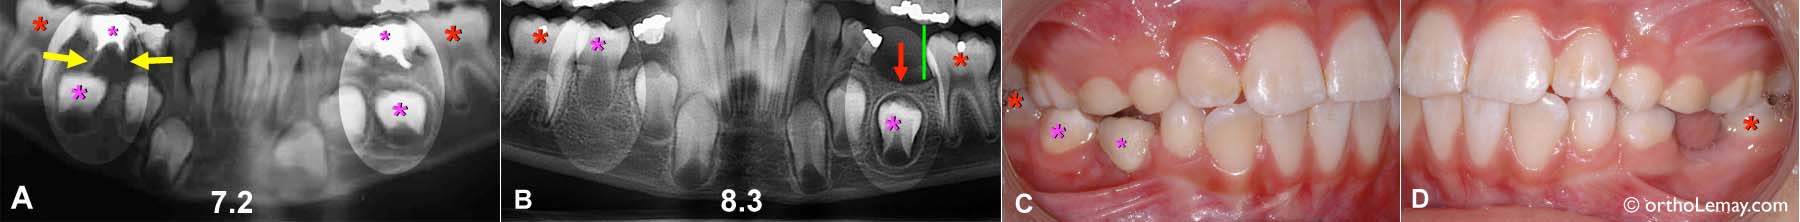

(A) Ce jeune patient de 7.2 ans avait une infection importante qui affectait la deuxième molaire temporaire inférieure droite (petit * rose). L’infection s’était déjà propagé au delà de la dent par les racines et commençait à détruire l’os alvéolaire autour des racines de la dent (flèches jaunes) et au dessus de la deuxième prémolaire (gros * rose) qui doit éventuellement remplacer la dent perdue.

En comparaison, du côté opposé (gauche du patient), bien que la même dent soit endommagée (petit * rose), il n’y a pas d’infection et de destruction osseuse.

(B) Peu de temps après la prise de la radiographie (A) la dent temporaire droite fut perdue car elle était devenue trop mobile suite à la perte d’os qui la supportait. Il se produisit alors un phénomène prévisible dans la mesure ou il n’y avait plus d’os recouvrant la prémolaire; ceci accélère l’éruption de la dent permanente même si sa racine est peu formée. Il est cependant surprenant est que la prémolaire ait pu compléter son éruption aussi rapidement (en moins de 12 mois) sans qu’il y ait eu migration vers l’avant de la molaire permanente (*rouge) et perte d’espace. Comme l’ont démontré les études de Moorees, une dent avec à peine le quart de sa racine formé n’est normalement pas prête à faire éruption mais l’absence d’os alvéolaire la recouvrant change complètement la donne.

Ce phénomène est très inhabituel et on ne peut espérer qu’il se produise dans la grande majorité des cas. C’est pourquoi il est toujours indiqué de préserver l’espace dans une telle situation, et même dans ce cas-ci, il aurait été souhaitable de poser un mainteneur d’espace inférieur.

La nouvelle radiographie prise à l’âge de 8.3 ans montre une seconde prémolaire droite complètement sortie mais avec une racine très courte. Du côté opposé. la dent temporaire fut aussi perdue mais en l’absence d’infection, il n’y a pas autant de perte osseuse et on peut voir de l’os (flèche rouge) recouvrant le bourgeon de la prémolaire (* rose). Cette dent prendra beaucoup plus de temps à faire éruption, probablement plus de 2 ans, alors il est indiqué de “bloquer” la molaire permanente (*rouge) à l’aide d’un mainteneur d’espace (illustré par la ligne verte).

(C) Situation clinique à 8.3 ans. Du côté droit, la prémolaire (gros * rose) est complètement sortie et en occlusion avec la dent opposée. Le petit astérisque rose indique la première molaire temporaire qui est toujours en bouche.

(D) Du côté gauche, il est préférable d’immobiliser la molaire (*rouge) pour éviter qu’elle ne bascule dans l’espace avant l’éruption de la prémolaire encore très basse dans la mâchoire.